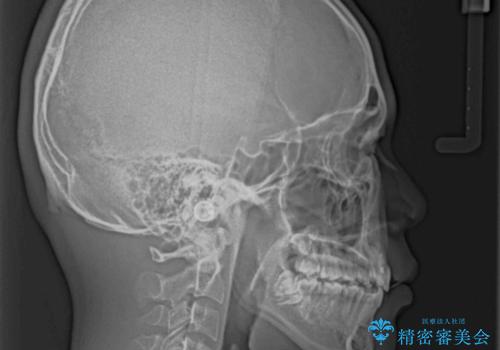

膨らんだ口元 ワイヤー装置での抜歯矯正

- 口元の突出感を気にして来院された患者様です。

上下前歯が著しく前突している状態であったので、上下左右の第1小臼歯4本を抜歯し、ワイヤー装置にて矯正治療を行うこととしました。

舌の突出癖により、前突になったと考えられたため、舌のトレーニングをしっかりと行うよう指導しました。

小学生の頃に上顎前歯をぶつけ、歯の一部が破損している状態であったので、歯根が歯槽骨と癒着して移動しない可能性がありましたが、無事に治療を終えることができました。

受験勉強と重なり、舌のトレーニングが十分に行えず、高校生としてはやや長期間の治療となりました。